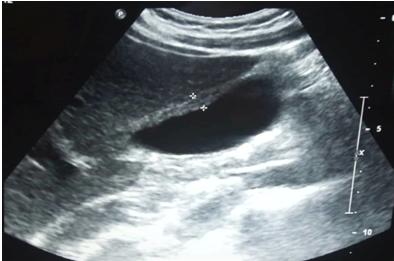

此外,患者的胸片正常。腹部超声显示胆囊壁厚12 mm,胆囊壁回声不均,但胆囊体积不大,其内未见结石。肝内外胆管未见扩张,有少量腹腔积液。

超声可能看不清结石,或者结石太小?然而,患者进一步接受腹部CT,结果显示胆囊壁增厚、胆囊体积增大,伴肝肿大,密度均匀。由此可见,急性胆囊炎毋庸置疑,但CT依然未发现结石!